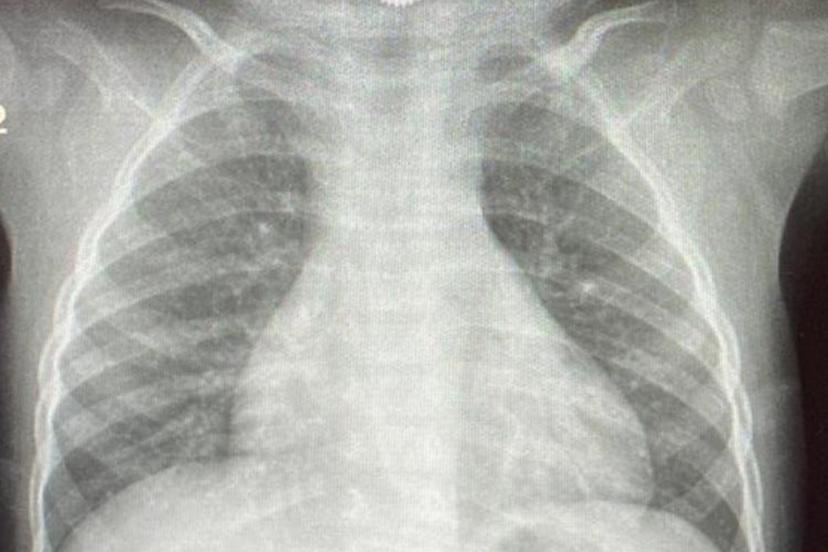

"Kimyasal maddelerin içilmesi de çocuklarda sık görülen ve ciddi sonuçlara yol açabilen bir durumdur. Özellikle yağ çözücü, lavabo açıcı gibi kimyasal maddeler çocuklar tarafından içilebilmekte ve ciddi yemek borusu yanıklarına neden olabilmektedir. Bilinenin aksine bu gibi durumlarda çocuk kesinlikle kusturulmamalıdır. Kusturma, yemek borusunda ikinci kez yanığa yol açabilmektedir. Böyle bir durumda çocuğa herhangi bir yiyecek ya da içecek verilmeden derhal sağlık kuruluşuna başvurulmalıdır. Evlerde kimyasal maddelerin plastik su şişelerine konulması, çocukların bu maddeleri içmesini kolaylaştırmaktadır. Bu tür durumlar ciddi yemek borusu ve damar yanıklarına neden olabilmektedir. Bu nedenle kimyasal maddelerin çocukların ulaşamayacağı, kilitli dolaplarda muhafaza edilmesi gerekmektedir."

Solunum yollarına yabancı cisim kaçmasının da önemli bir risk olduğuna dikkat çeken Özkaya "Solunum yollarına yabancı cisim kaçması da günlük hayatta sık karşılaşılan ve hayati tehlike oluşturabilen durumlardan biridir. Özellikle üç yaşına kadar olan çocuklara çerez, fındık, fıstık, çekirdek gibi sert gıdaların verilmemesi gerekmektedir. Bu gıdalar solunum yollarına kaçarak ciddi nefes darlığına neden olabilmektedir. Böyle bir durumla karşılaşıldığında, mümkünse Heimlich manevrası uygulanmalı ve 112 Acil Servis eşliğinde en yakın sağlık kuruluşuna başvurulmalıdır. Bu tür vakaların operasyon gerektirebileceğine dikkat çekilerek, özellikle yemek borusunda kalan disk pillerin son derece tehlikeli olduğu vurgulanmaktadır. Disk piller, çocukta belirgin bir şikâyet olmasa bile kısa sürede yemek borusunda yanıklara ve delinmelere yol açabilmekte, hayati risk oluşturabilmektedir. Bu nedenle acil olarak ameliyathane ortamında çıkarılmaları gerekmektedir." şeklinde konuştu.